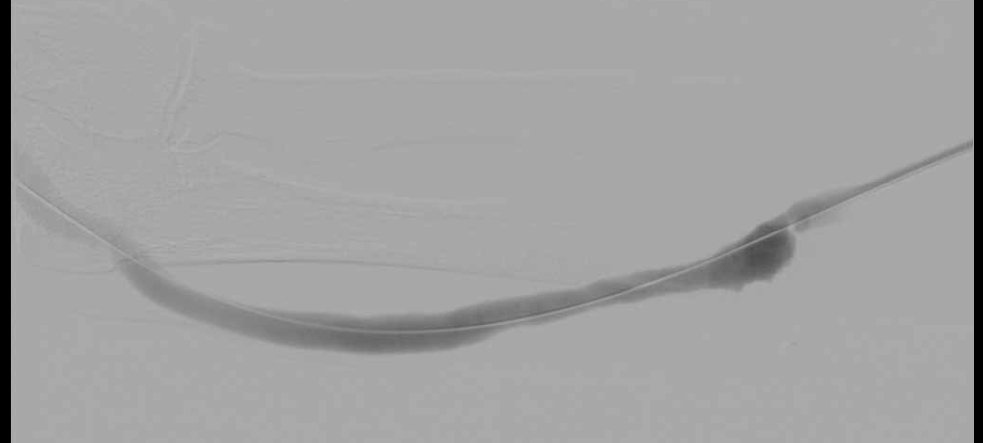

시술 전

시술 후